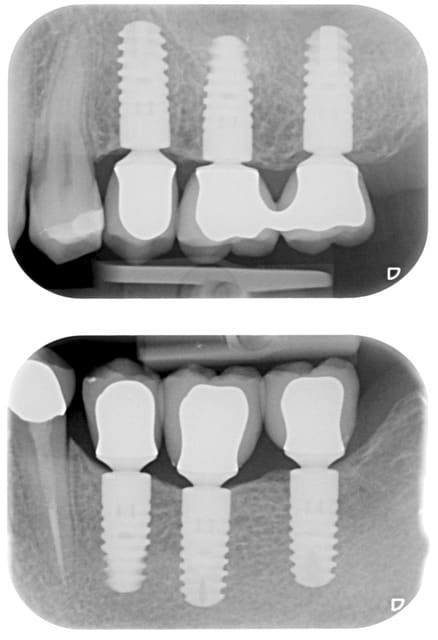

Oui, voici les radios

Pour la 4 (22) au tout début j'avais fait une ccc, mais le collet malgré une chape opaque était grisé, on a donc refait une ccm!

La CCM du 4 se voit facilement, les autres non, et pour cause, soit il y a du Margin (3), soit c'est de la prothèse supra implantaire et il y a donc plus de place en général pour que la prothésiste gère sa stratification et sa morpho